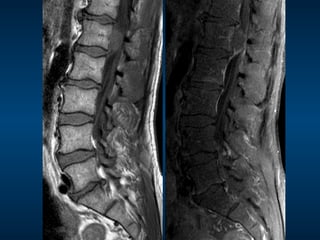

•  68M •  Suddenonset bilateral leg pain and weakness •  Urinary retention MRI

•  Dx: Caudaequina syndrome •  Cause: massive sequestration •  Other causes: – Tumour •  Primary of lower cord, nerve, dura, vertebral body •  Secondary – Trauma